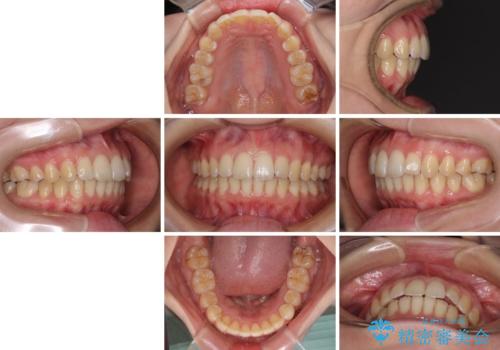

- 上下前歯のデコボコと深い咬み合わせを気にして来院された患者様です。

インビザラインによる上下歯列の拡大と、IPR(歯と歯の間を削る)にるスペースの獲得により、前歯のデコボコを改善することとしました。

上の前歯をもう少し整えたかったのですが、患者様の治療を早く終了させたいという希望により、細かい叢生を残しての終了となりました。